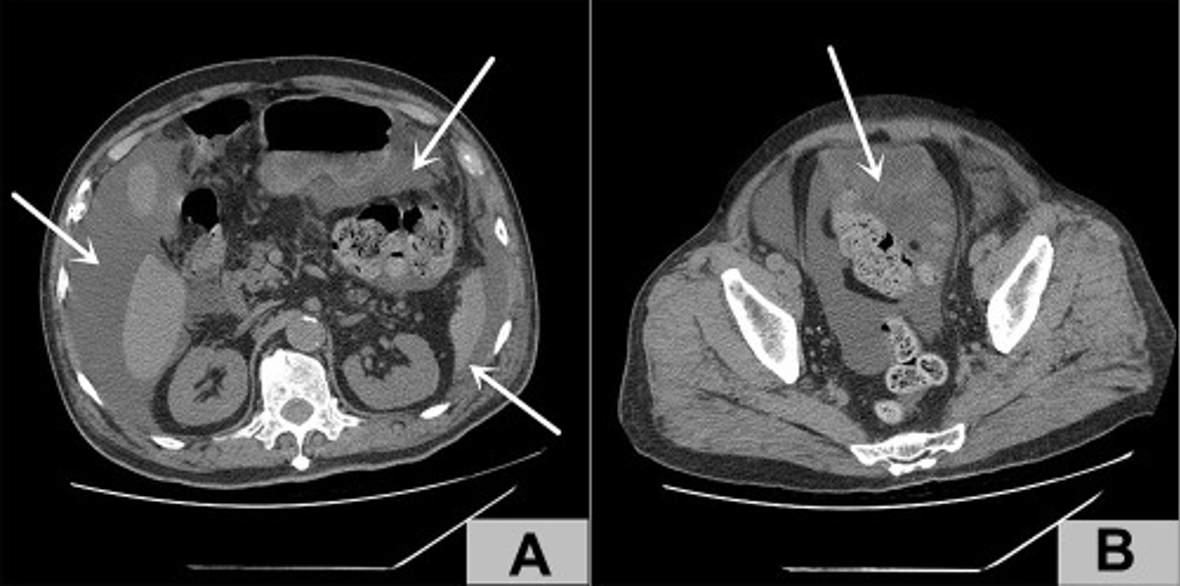

Das ärztliche Team vor Ort wollte den Defäkationsschwierigkeiten auf den Grund gehen und führte eine digital-rektale Untersuchung durch. Es zeigte sich lediglich eine vergrößerte Prostata ohne tastbare Knoten. Weiterführende Untersuchungen ergaben einen massiven Aszites: Mittels abdominaler Computertomographie (CT) konnte eine große Flüssigkeitsmenge im Bereich des Abdomens und Beckens dargestellt werden. Der Dickdarm war prall gefüllt. Das ärztliche Team dachte erst zu diesem Zeitpunkt an eine Blasenruptur als Folge der Varizella-Zoster-Infektion – bis dato gab es so einen Fall noch nie.1

Abbildung 2: Im Bildabschnitt A markieren die weißen Pfeile die Flüssigkeitsansammlung im Abdomen. Der weiße Pfeil in Bildabschnitt B zeigt auf die Stelle, an der die Blasenruptur vermutet wurde.1